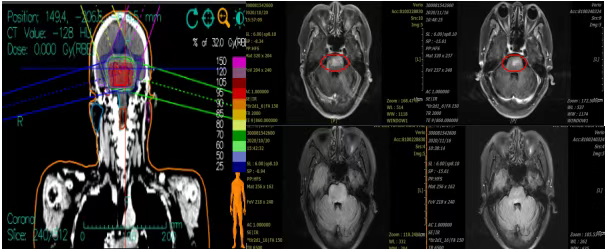

Case 1: A 72-year-old female patient presented with complaints of "decreased muscle strength in the right limb, hoarseness, choking when drinking water, and double vision for 5 months." A head MRI indicated a space-occupying lesion in the brainstem, measuring approximately 2.7 * 3.3 cm, suspected to be a glioma. Diagnosis: Brainstem glioma. Carbon ion radiotherapy was initiated on October 26, 2020.

The patient's treatment concluded on November 12, 2020. The patient showed a significant increase in limb muscle strength, and symptoms such as hoarseness, drinking cough, and binocular diplopia were alleviated. A review of the head MRI indicated that the brainstem glioma had decreased in size compared to before treatment, measuring approximately 2.0 * 3.1 cm, with enhanced weakening and no significant edema.